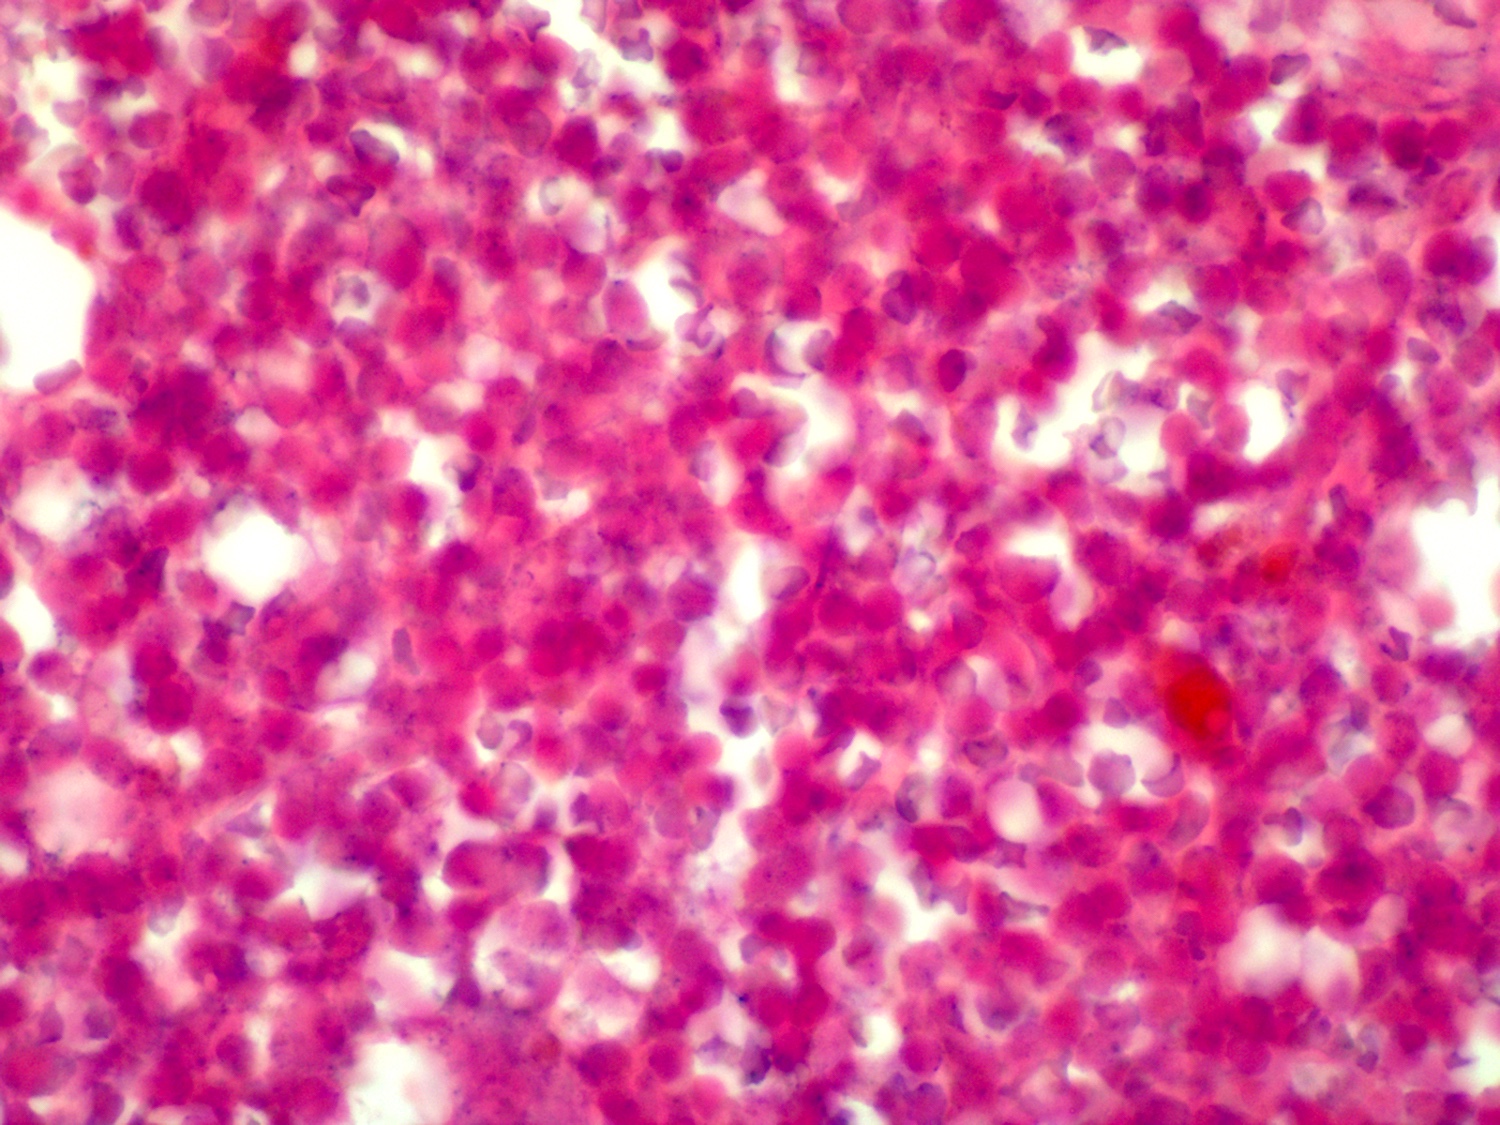

Microscopic (histologic) description

- Blood

- Often shows lymphocytosis with a spectrum of lymphocytes, plasmacytoid lymphocytes and plasma cells

- Rouleaux formation of red blood cells is routinely seen

- Cold agglutinin or cryoglobulin may be present

- Bone marrow (Arch Pathol Lab Med 2013;137:580)

- Involvement in almost all cases

- Aspirate is the most helpful sample in morphologic diagnosis

- Predominantly small lymphocytes with a variable number of plasmacytoid lymphocytes and plasma cells

- Mast cells are typically increased; most prominent within particles on aspirate smears

Microscopic (histologic) images

Contributed by Ling Zhang, M.D.